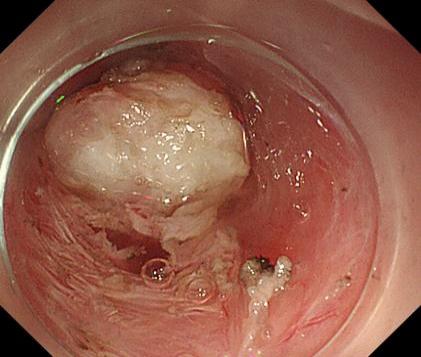

胃底間質瘤 內鏡下全層切除術后創面 切除后標本

內鏡下全層切除術(EFTR):治療消化道黏膜下腫瘤(最主要):起源于固有肌層深層、部分腔外生長、與漿膜層密不可分;少部分抬舉征陰性消化道癌前病變和早期癌;少部分困難解剖部位結腸病變(如結腸憩室內腺瘤)等。